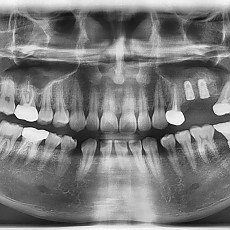

시술전후사진 2 페이지

시술전후사진

Total 62건 2 페이지